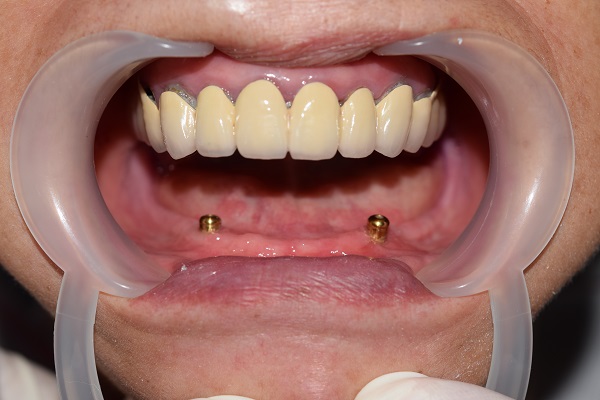

蔡女士坚持只要有一线希望就不会放弃,她说自己会全力配合医生的治疗方案,也能理解相应的并发症及可能不太佳的修复效果。有了患者的充分信任,王主任和傅医生通力合作,先对患者凹凸不平的牙槽骨进行修整并切除过多增生的松软牙龈,根据口腔修复学原理,在CT指示下,在其下颌双侧尖牙区发现两个仅有的可用种植位点,拟采用目前国内外最为先进的种植修复方式,即种植体支持式Locator球帽固位的下颌半口义齿修复下颌牙列缺失。

根据术前设计的治疗方案,通过牙槽嵴平整术、植体植入及形成良好的骨结合、二期牙龈手术,袖口形成,模型制取,二次印模,咬合记录,试牙、戴牙等一系列精细的程序,历时大半年多,蔡女士终于戴上了梦寐以求的义齿,无论是咬合、前牙覆盖、笑线及面容外观她都非常满意。她俏皮地说“没想到我还能等到自己有牙的一天,家人为了庆祝我能吃东西,专门请我大聚餐,我终于告别了吃肉糊的日子啦”。